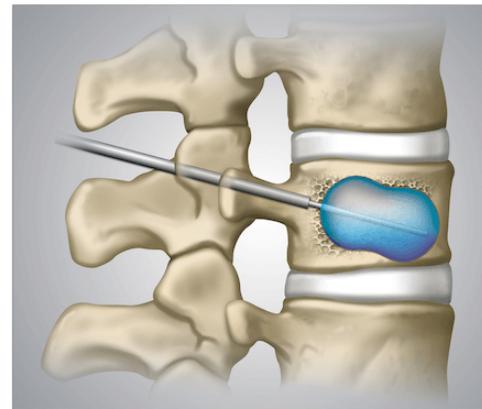

- Kyphoplasty: Reserved for patients with recalcitrant symptoms after 4-6 weeks of nonoperative treatment